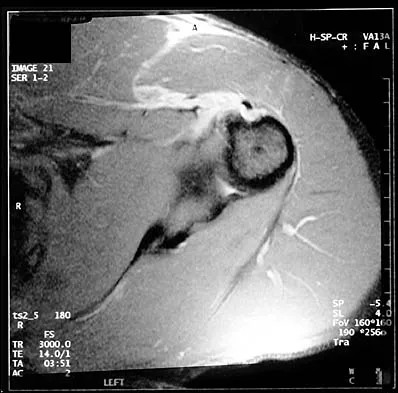

Question 420High Yield

A 29-year-old man who lifts weights states that he injured his left shoulder while performing a bench press 2 days ago. The following morning he noted ecchymosis and swelling in the left chest wall. Examination reveals ecchymosis and tenderness and deformity in the left anterior chest wall and axillary fold that is accentuated with resisted adduction of the arm. Passive range of motion beyond 90 degrees of forward flexion and 45 degrees of external rotation is extremely painful. Glenohumeral stability is difficult to assess because of severe guarding. Figure 29 shows an MRI scan. Management should consist of

Explanation

Rupture of the pectoralis major tendon most commonly occurs during bench pressing. Wolfe and associates have shown that the most inferiorly located fibers of the sternal head lengthen disproportionately during the final 30 degrees of humeral extension during the bench press. This creates a mechanical disadvantage in the final portion of the eccentric phase of the lift; with forceful flexion of the shoulder these maximally stretched fibers may rupture. In most patients, particularly in young athletes, the treatment of choice is anatomic repair of the ruptured tendon to its insertion in the proximal humerus either with suture anchors or transosseous sutures. Following surgery, most patients experience a near normal return of strength and significant improvement in the cosmetic appearance of the deformity. While more technically challenging, repair of chronic rupture is possible and is indicated in some patients. Wolfe SW, Wickiewicz TL, Cavanaugh JT: Ruptures of the pectoralis major muscle: An anatomic and clinical analysis. Am J Sports Med 1992;20:587-593.